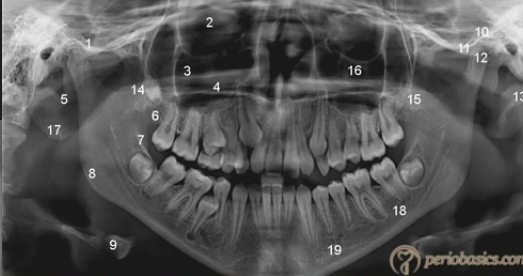

what are the normal anatomic landmarks

bony landmarks of maxilla, mandible, and surrounding strucutures

air spaces and soft tissues seen on pano images

what are the bony landmarks of the maxilla and surrounding structures

mastoid porcess

styloid process

external auditory meatus

glenoid fossa

articular eminence

lateral pterygoid plate

pterygomaxillary fissure

maxillary tuberosity

infraorbital foramen

orbit

incisive canal

incisive foramen

anterior nasal spine

nasal cavity

nasal septum

hard palate

maxillary sinus

floor of maxillary sinus

zygomatic process

zygoma

hamulus

what are the bony landmarks of the mandible and surrounding structures

mandibular condyle

coronoid notch

coronoid process

mandibular foramen

lingula

mental foramen

mental ridge

mental fossa

lingual foramen

genial tubercles

inferior border of the mandible

mylohyoid ridge

external oblique ridge

angle of the mandible